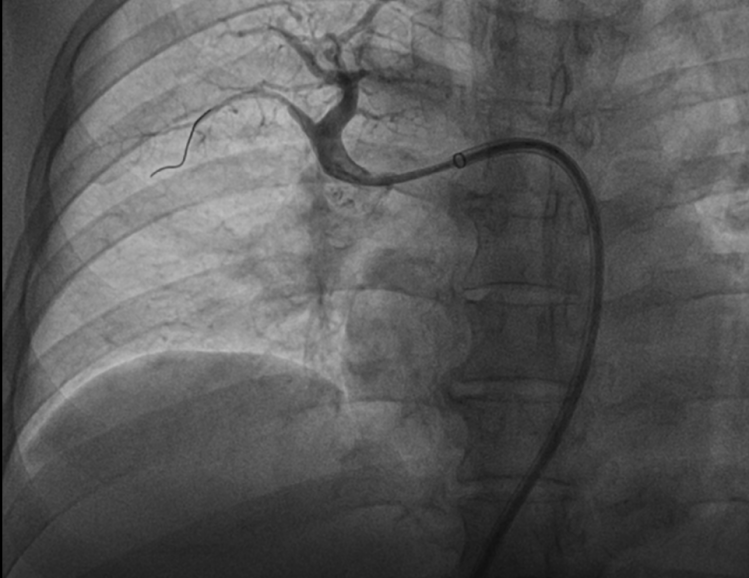

患者慕名至我院后,我科专家进一步对其进行了相关检查,最终诊断为:慢性血栓栓塞性肺动脉高压。心内科周亚峰副院长、陈弹主任、赵良平主任及团队成员进行深入讨论,并邀请呼吸科、血管外科与介入科等进行多学科(MDT)会诊,最终决定对其进行右心导管及肺动脉造影检查,结果提示肺动脉收缩压52mmHg,平均肺动脉压33mmHg,左右各肺动脉及其分支多发栓塞,可见多处血栓影及马赛克征。对右肺动脉A3、左肺动脉A1+2、左肺动脉A9行球囊扩张术,扩张后复查造影远端血流恢复良好。手术后患者的症状得到明显改善,心功能逐渐恢复,住院5天后平稳出院。出院后患者继续进行家庭氧疗、抗凝、利奥西呱降肺动脉压力等治疗,并密切随访中。随访至今,患者情况良好。

扩张后